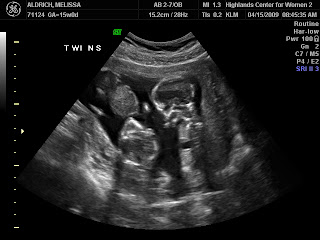

to looking like sweet babies!

The miracles of God knitting little ones in my womb is just incredible to watch by ultrasound!

Do you think they’ll be identical or not based on these photos?